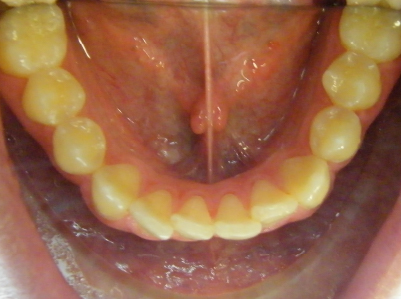

Patient 1: Severe upper and lower crowding with congenitally missing two lower adult teeth and a crossbite.